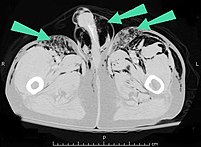

Significant cases of subcutaneous emphysema are easy to diagnose because of the characteristic signs of the condition.[1] In some cases, the signs are subtle, making diagnosis more difficult.[13] Medical imaging is used to diagnose the condition or confirm a diagnosis made using clinical signs. On a chest radiograph, subcutaneous emphysema may be seen as radiolucent striations in the pattern expected from the pectoralis major muscle group. Air in the subcutaneous tissues may interfere with radiography of the chest, potentially obscuring serious conditions such as pneumothorax.[18] It can also reduce the effectiveness of chest ultrasound.[27] On the other hand, since subcutaneous emphysema may become apparent in chest X-rays before a pneumothorax does, its presence may be used to infer that of the latter injury.[13] Subcutaneous emphysema can also be seen in CT scans, with the air pockets appearing as dark areas. CT scanning is so sensitive that it commonly makes it possible to find the exact spot from which air is entering the soft tissues.[13] In 1994, M.T. Macklin and C.C. Macklin published further insights into the pathophysiology of spontaneous Macklin's Syndrome occurring from a severe asthmatic attack.